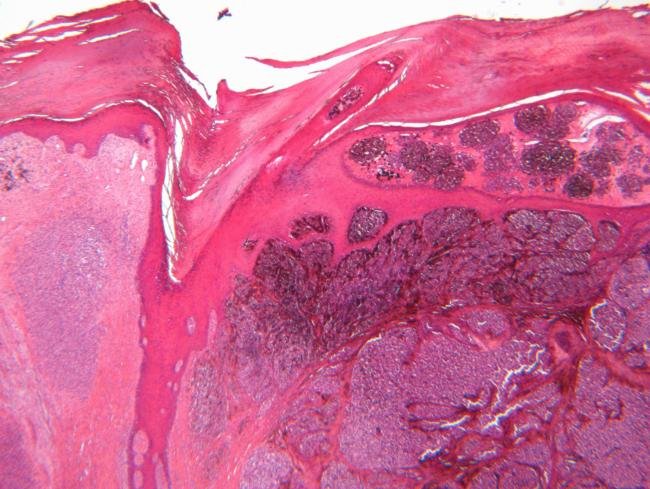

Researchers educated their mannequin on single-cell datasets paired with survival information from a whole lot of sufferers. They then examined it on scientific information from sufferers with melanoma or liver most cancers and located it predicted outcomes extra precisely than conventional strategies.

The crew additionally traced the mannequin’s predictions again to particular cell teams, figuring out immune and tumor cells linked to raised or worse survival. In melanoma, they recognized cell populations related to responses to immunotherapy.